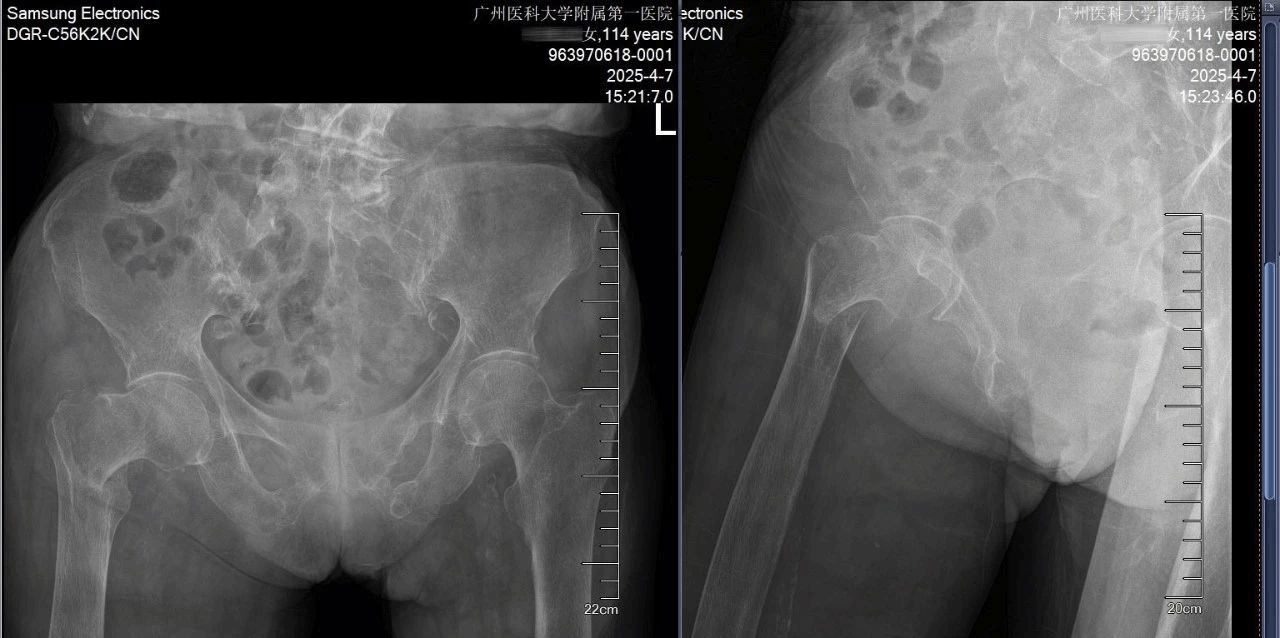

术前全面评估,患者术前有下肢DVT、肺部感染、慢性心功能不全、中度贫血、低蛋白血症,X线片显示股骨皮质极薄、股骨髓腔呈“烟筒样”改变。术前多学科会诊并给予抗凝、控制肺部感染、改善贫血和低蛋白血症、治疗骨质疏松、改善心功能,为麻醉、手术治疗创造条件。

经过精心术前准备,患者各项指标明显改善,考虑到患者骨质疏松非常严重和早期下地活动的要求,经多学科讨论,并且与家属充分沟通和慎重考虑,卢伟杰团队最终决定采用水泥型人工股骨头置换术进行治疗。

术前术后X光照片